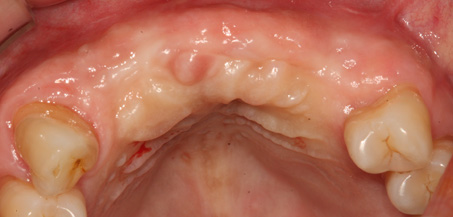

치조골 이식술 전후사진

B

A